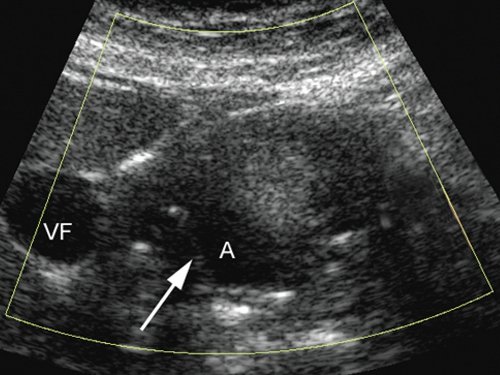

При комплексном УЗИ в В-режиме визуализировали округлое образование в капсуле различной степени выраженности, неоднородное по структуре, по периферии преимущественно эхоплотное с наличием анэхогенной полости, интимно прилежащей к одной из стенок с нарушением ее целостности. При дуплексном сканировании отмечено спонтанное контрастирование полости аневризмы (аналогично и в режиме Sie-flow) с регистрацией артериального кровотока. В режиме импульсной допплерографии линейная скорость кровотока на входе в аневризму была повышена на 18,9-37,8% по сравнению с нормальными значениями с высокой диастолической составляющей. В 18 случаях полость аневризмы окрашивалась не полностью, имелись пристеночные неокрашиваемые участки, которые соответствовали "свежим" тромботическим массам (рис. 1).

Полость аневризмы (А) в режиме ЦДК не окрашивается, в ней определяются линейные гиперэхогенные структуры. Контуры кисты нечеткие, ровные (VF - желчный пузырь).

Контрольное УЗИ также было проведено через 45 дней после эндоваскулярного вмешательства. В режимах ЦДК и ЭОДС просвет данной полости не окрашивался (рис. 11).

Полость аневризмы (А) в режиме энергии отраженного допплеровского сигнала не окрашивается. По внутреннему латеральному контуру полости определяются округлые гиперэхогенные структуры (указаны стрелками), контуры кисты четкие, ровные (продольное сканирование, VP - воротная вена).